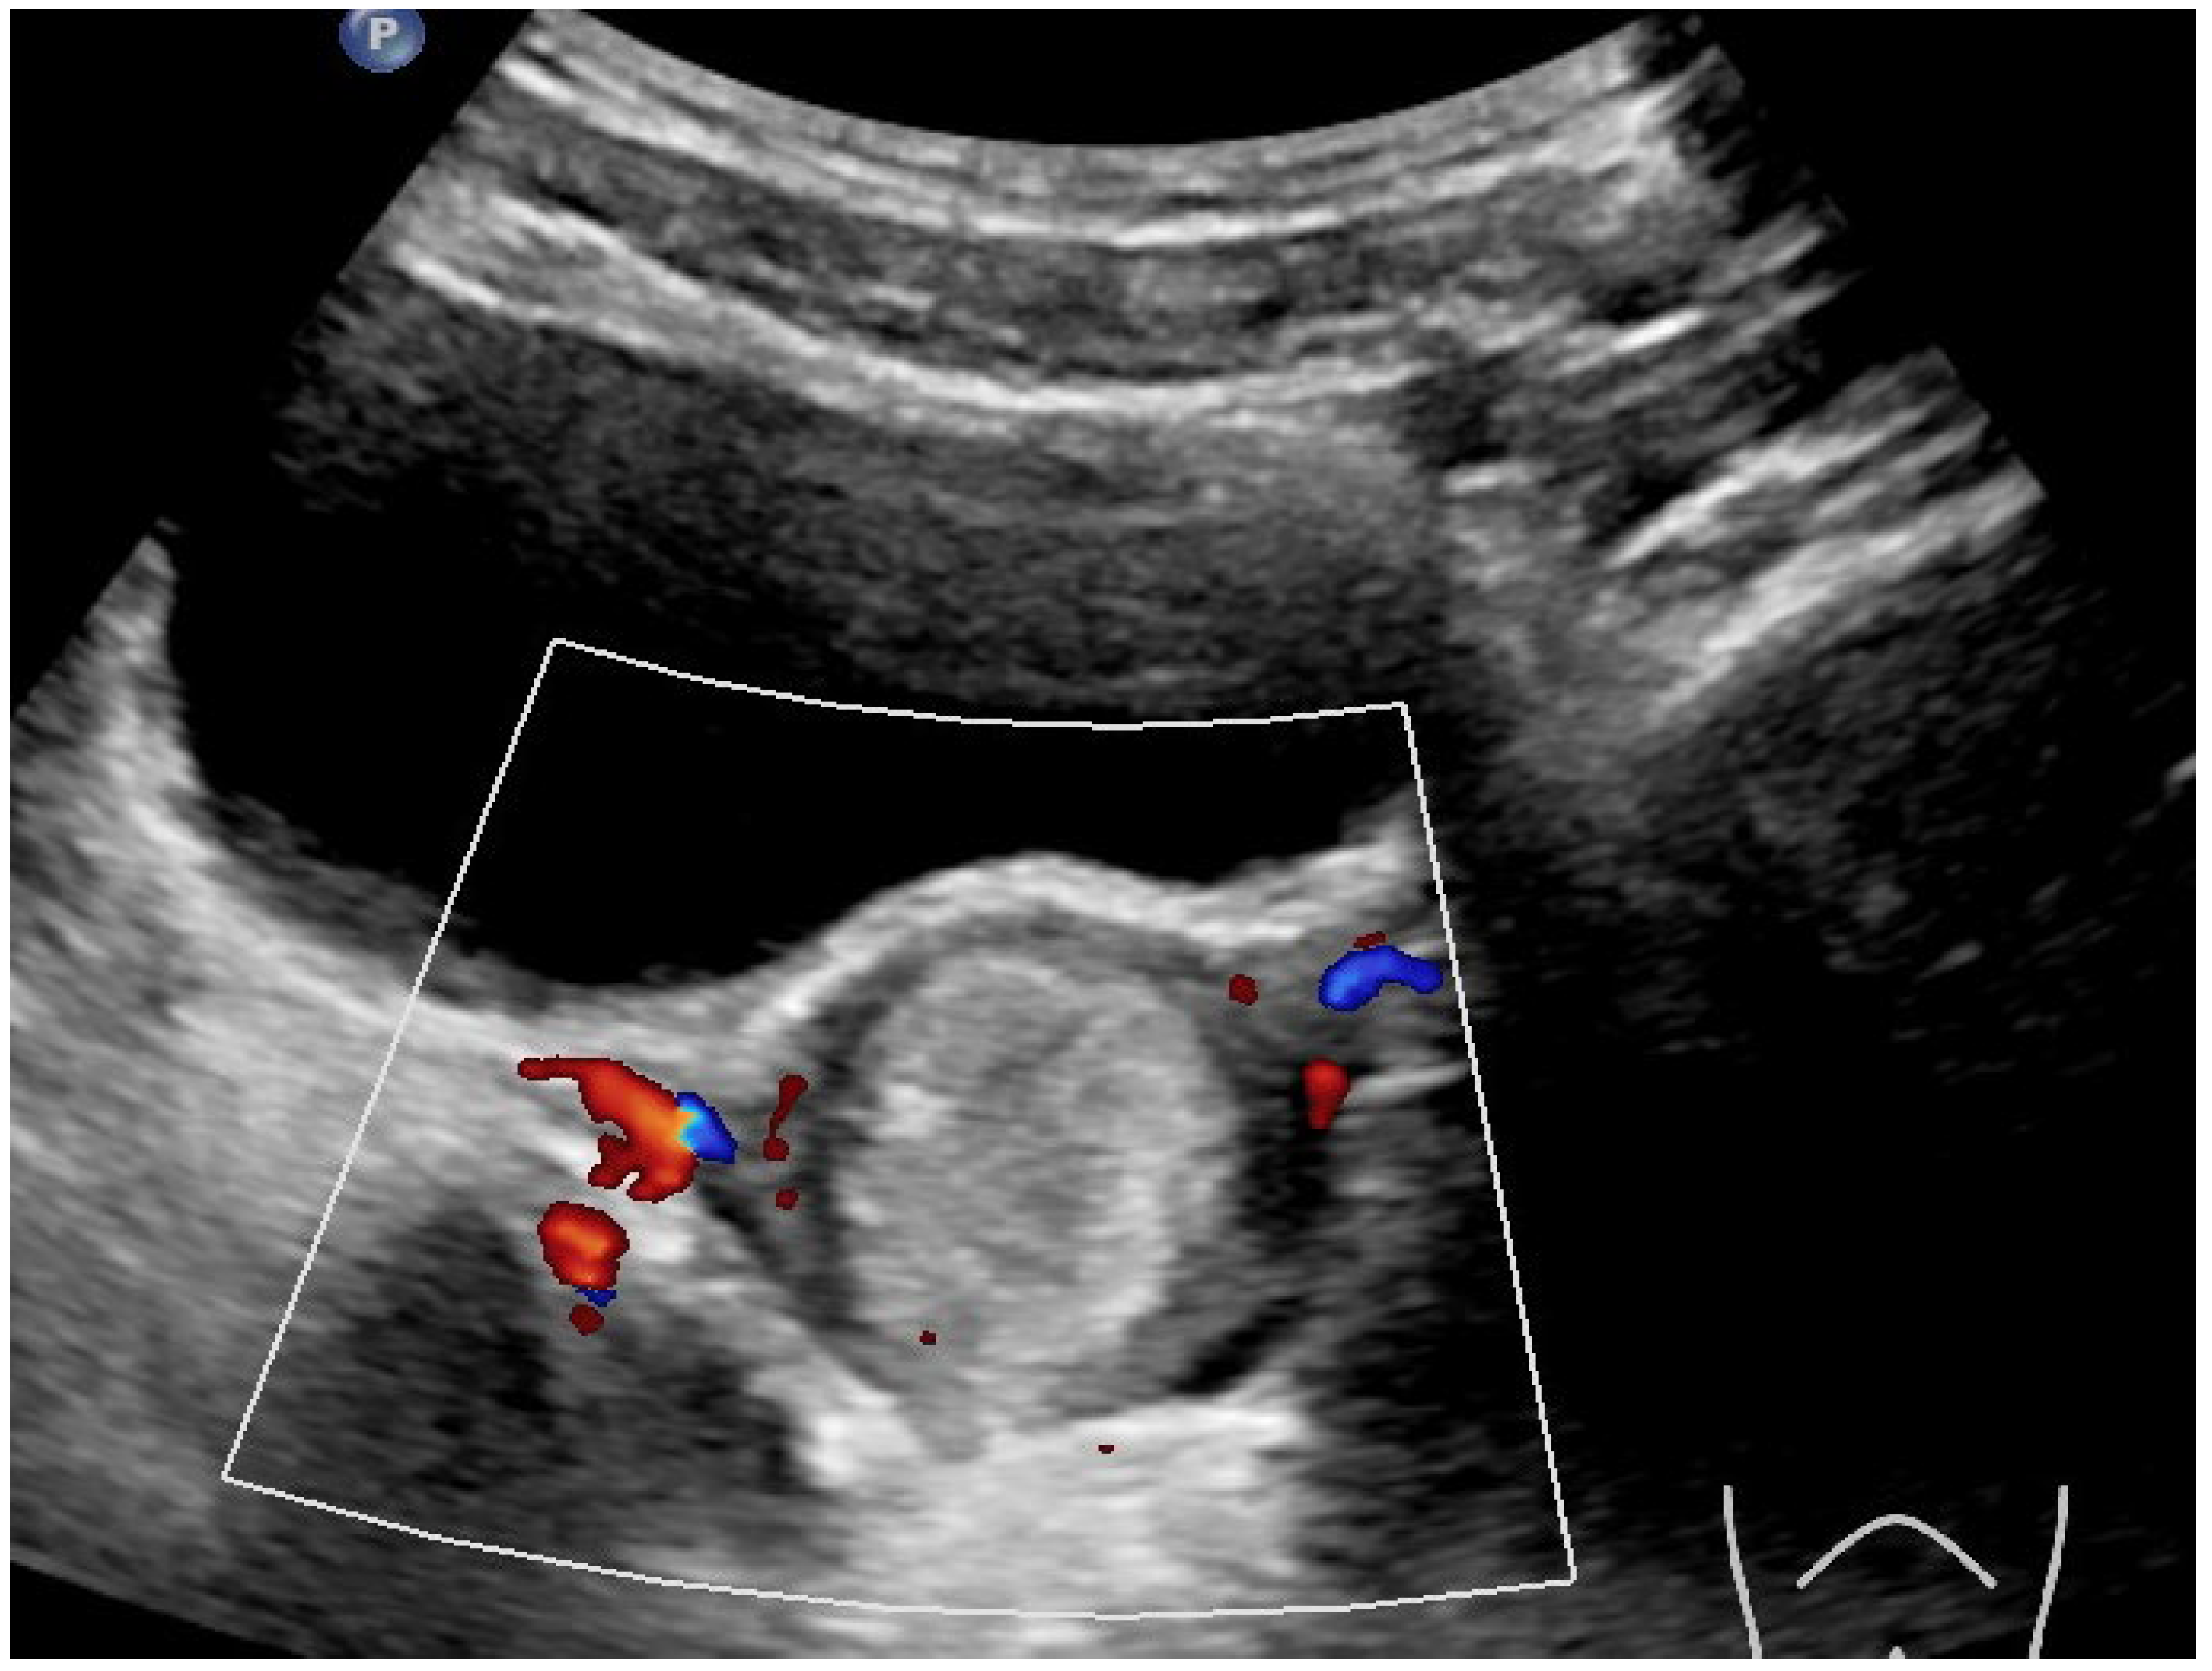

Results and Discussion: A healthy 9 year old girl was referred to our outpatient clinic of Pediatric Gynecology because of vaginal bleeding since two months, without trauma and accompanied by mild abdominal discomfort. She suffered from daily vaginal bleeding, varying from spotting to small blood clots. No vaginal discharge, pruritus, fever or constipation. She did not use medication. Physical examination showed a 1.29 m height girl, weighing 28 kg with Tanner stage 1. Genital examination showed normal prepubertal external genitalia without skin lesions or vaginal discharge. A vulvovaginal sample for bacterial culture was normal. Abdominal ultrasound showed an enlarged uterus with a 2.2 cm hyperechogenic intracavitary mass without blood flow (Figure 1) and normal ovaries. It was concluded to be hematometra. MRI confirmed normal development of internal genitals and hematometra. Blood results were (repeatedly): Hb 7.0 mmol/L; FSH 0.7 IU/L; LH < 0.1 IU/L; estradiol < 20 pml/L. Normal values of infection markers, tumor markers, thyroid function and testosterone. Hysteroscopy was performed under general anesthesia and showed a round, pale pedunculated intracavitary structure. Biopsies showed a thrombus, without signs of malignancy. In a following hysteroscopy the structure was completely removed without significant blood loss. The pathology report showed a benign capillary-venous malformation.

Figure 1.

Abdominal ultrasound.